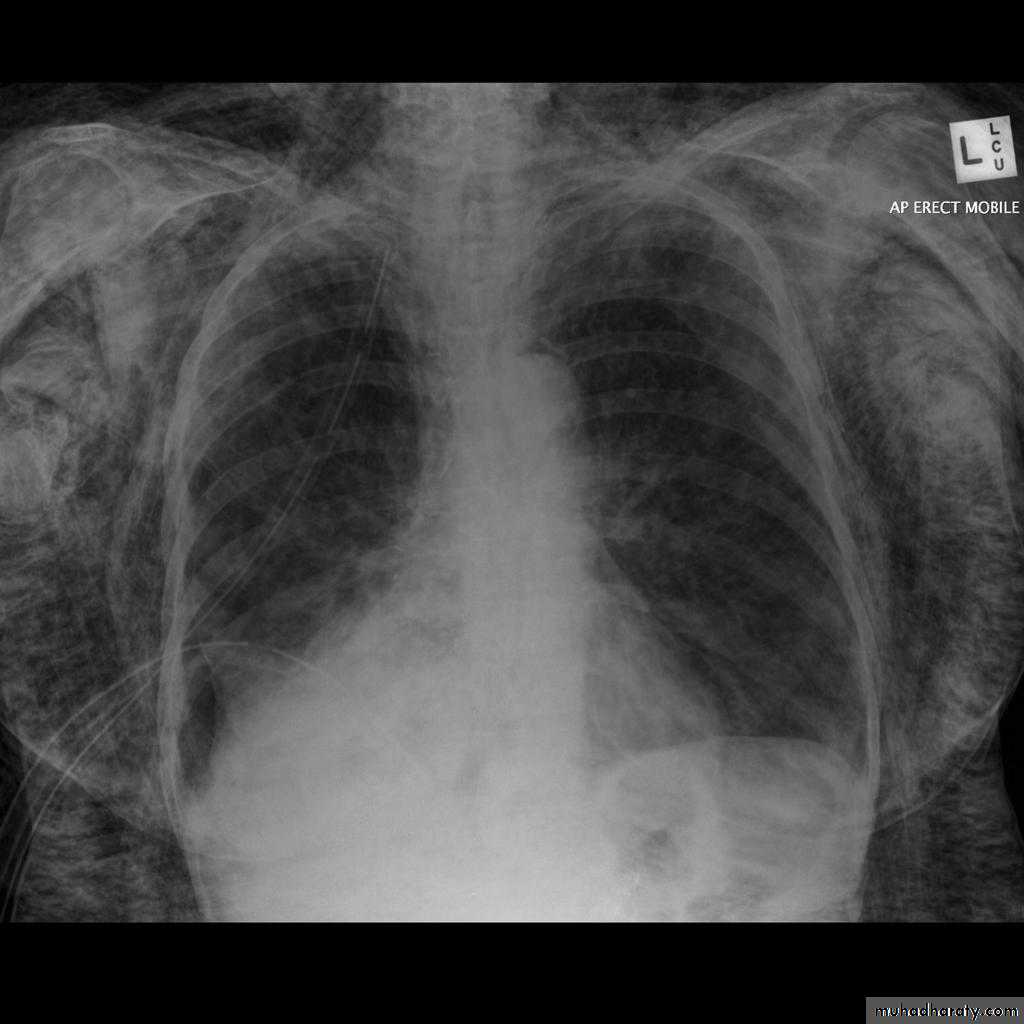

Left lower lobe collapse has distinctive features, and can be readily identified on frontal chest radiographs, provided attention is paid to the normal cardiomediastinal contours. The shadow cast by the heart does however make it harder to see than the right lower lobe collapse

Radiographic features

Left lower lobe collapseis readily identified in a well penetrated film of a patient with normal sized heart, but can be challenging in the typical patient with collapse, namely unwell patients, with portable (AP) often under-penetrated films, often with concomitant cardiomegaly. Features to be observed include :

triangular opacity in the posteromedial aspect of the left lung

edge of collapsed lung may create a 'double cardiac contour'

left hilum will be depressed

loss of the normal left hemidaphgragmatic outline

loss of the outline of the descending aorta

Non-specific signs indicating left sided atelectasis are usually also be present including:

elevation of the hemidiaphragm

crowding of the left sided ribs

shift of the mediastinum to the left

On lateral projection the left hemidiaphragmatic outline is lost posteriorly and the lower thoracic vertebrae appear denser than normal (they are usually more radiolucent than the upper vertebrae) .